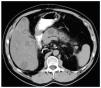

En la TAC abdominal se identificó una masa quística de contorno multilobulado en región del cuello de páncreas, de aproximadamente 4,7 x 3,7 cm condicionando una dilatación del conducto pancreático a nivel de cuerpo y cola de páncreas (fig. 1).

Figura 1.